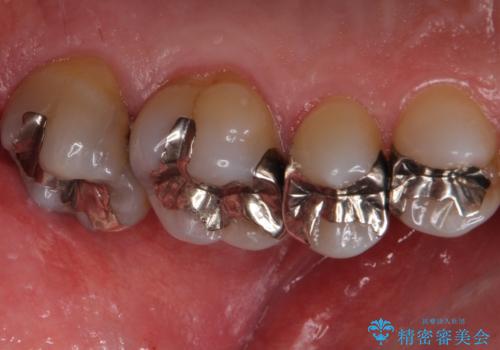

ゴールドの詰め物や被せ物はかなり精度よく仕上がります。

外から見えにくい上の奥歯に特におすすめです。

また、歯と歯の間は虫歯の好発部位です。

歯磨きに加え、フロスや歯間ブラシを通す習慣をつけましょう。